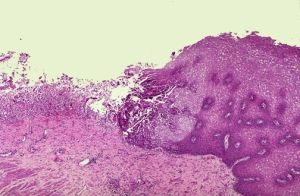

單純皰疹病毒(HSV)引起的傳染病。HSV可分1型(HSV-1)和2型(HSV-2)。常見的HSV感染有復發性口唇皰疹、皮膚皰疹、急性皰疹性口齦炎和急性皰疹性角膜結膜炎。少見的有急性皰疹性神經系統感染如腦膜炎、腦炎、脊髓炎和神經根炎。新生兒和免疫功能低下者常表現為嚴重的全身性HSV感染。皰疹性腦炎病情重病死率高,有的可造成終身殘疾。HSV感染十分普遍,根據對人群中HSV抗體的調查,約90%10歲兒童血清中有HSV抗體,成人可達100%,這說明他們已經受過HSV感染。西方國家,如美國及一些西歐國家,HSV-2引起的生殖器皰疹,作為性傳染病而流行,患有生殖器皰疹的婦女所生的新生兒,可以發生全身性播散性皰疹感染及皰疹性腦炎,其病死率極高或留有嚴重的後遺症。一些器官移植和接受免疫抑制劑及抗腫瘤藥治療的病人,由於免疫功能低下,可泛發全身性皰疹感染乃至死亡。此外,不少的資料證明,HSV-1感染可能與唇癌有關,而HSV-2感染則可能與子宮頸癌的發生有關,因此世界各國都十分重視對HSV及其感染的研究和控制。

單純皰疹病毒屬皰疹病毒科,分HSV-1和HSV-2兩型,完整的病毒顆粒呈球形,直徑為120~150nm,病毒核心部分由雙股DNA和一些蛋白質構成,外有蛋白質外殼,由162個殼微粒組成六角形立體對稱的20面體,最外一層為包膜,由糖蛋白和脂肪組成。糖蛋白具有HSV的抗原性,並與病毒附著及穿透寄主細胞的能力有關。HSV對溫熱、紫外線、乙醚、氯仿均很敏感,對HSV敏感的動物有家兔、小鼠(尤其是乳鼠)、豚鼠、大鼠和地鼠等。可用雞胚絨毛尿囊膜、人胚腎和兔腎細胞及小白鼠腹腔和腦內接種的方法分離病毒。人是HSV的唯一寄主。原發性感染和復發性感染病人及無症狀的排病毒者均可成為傳染源,約有20%健康幼兒和1~5%的成人是無症狀排病毒者,從其唾液中可分離出HSV。有的國家常規宮頸陰道細胞學檢查發現,約有0.5%婦女從生殖器排出HSV,因此,無症狀排病毒者十分普遍。